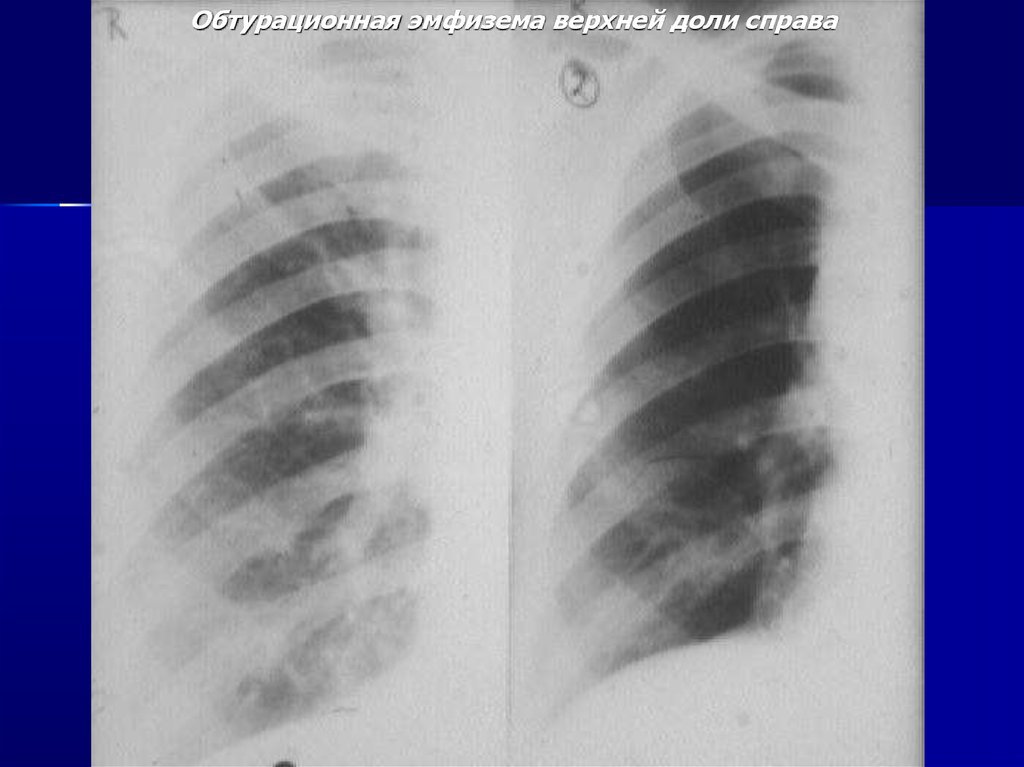

Обтурационная эмфизема верхней доли справа

Ателектаз верхней доли справа